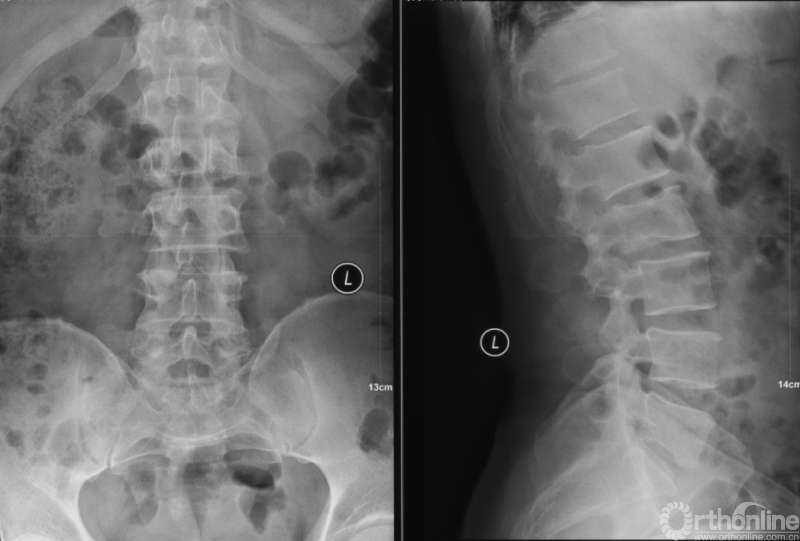

患者房某,男性、51岁。主因“腰痛3个月”入院,既往外院诊断“周围型肺腺癌”,全身检查提示多发骨转移。

经Spine Oncology Study Group(SOSG)评估硬膜外脊髓压迫(ESCC)为Grade 1a型,轻度脊髓压迫;脊柱机械稳定性评估(SINS)7分,中度不稳。修正Tokuhashi评分(RTS)6分,预计生存<6个月,建议姑息性手术及保守治疗;结合Tomita评分系统6分,故行姑息性手术短期控制。

影像学资料

PVP治疗